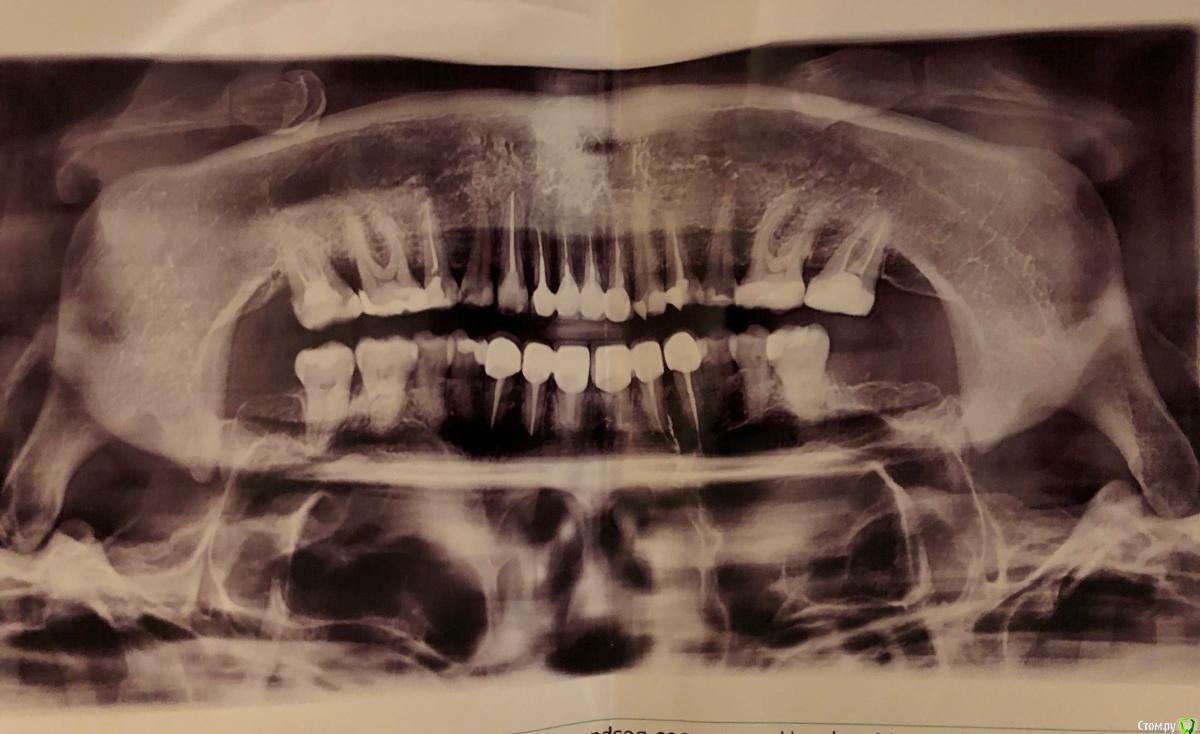

Vikalants Опубликовано 7 января, 2021 Поделиться Опубликовано 7 января, 2021 Здравствуйте, уважаемые доктора! С новым годом! Меня зовут Виктория, мне сейчас 38. У меня СОЭ 56 по состоянию на 4.01.2021. Летом 2020 - 32. С 2011 года, а может и раньше высокое соэ, 30-48. Несколько раз у меня была гранулема, один раз оперировали, второй раз пролечили. Летом 2019 года соэ 4. Уважаемые доктора, пожалуйста, посмотрите может у меня опять гранулема (прилагается панорамный снимок)? Гниет челюсть? Что делать, если это так, резекцию и заполнить костной тканью? Тогда я буду знать от чего отталкиваться и к кому идти. Почему у меня так, из-за чего, происхождение неизвестно. А может ли это быть, потому что ударилась челюстью на льду?28 лет назад я упала на льду, ударилась нижней челюстью об железку и сомкнулась челюсть, отвалились кусочки передних верхних зубов, треснули они также. Много лет болели, ныли. Местные доктора хотели их удалить, я отказалась. И только через 10 лет после падения обнаружили кисты на корнях этих зубов. Резекцию сделали. Потом через еще десять лет на соседнем зубе. И после опять. Дает ли гранулемы высокое СОЭ? Ссылка на комментарий

DmitrySH Опубликовано 9 января, 2021 Поделиться Опубликовано 9 января, 2021 По данному снимку сложно что-то конкретное сказать. Что беспокоит? Ссылка на комментарий

DmitrySH Опубликовано 9 января, 2021 Поделиться Опубликовано 9 января, 2021 post-49841-0-21351700-1610060233.jpeg Да снимок вверх ногами можно посмотреть, это не проблема. Но на нем сложно что-то конкретное разобрать Ссылка на комментарий